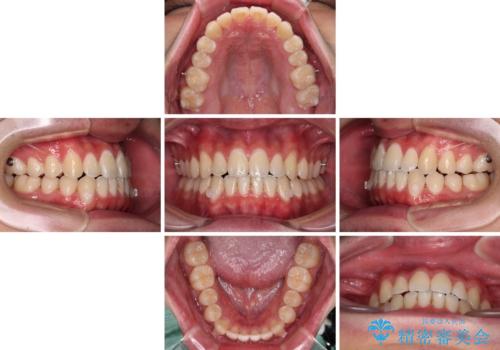

- 前歯のデコボコを治したいとのことで来院された患者様です。

受け口傾向の骨格であり、前歯はクロスバイトまたは切端咬合となっており、叢生は警備であったため、下顎を中心に歯列全体の後方移動を行い、IPR(歯と歯の間を削る)によってデコボコが解消するように設計し、インビザラインにより治療を行うこととしました。

受け口傾向のインビザライン矯正は比較的治療を行いやすいため、きれいに仕上げることができました。舌の突出癖が顕著であったため、改善のためのトレーニングをしっかりと行っていただきました。